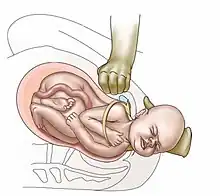

| Suprapubic pressure being used in a shoulder dystocia | |

Shoulder dystocia is when, after vaginal delivery of the head, the baby's anterior shoulder gets caught above the mother's pubic bone.[3][1] Signs include retraction of the baby's head back into the vagina, known as "turtle sign".[1] Complications for the baby may include brachial plexus injury, or clavicle fracture.[2][1] Complications for the mother may include vaginal or perineal tears, postpartum bleeding, or uterine rupture.[3][1]

- Anterior shoulder disimpaction (suprapubic pressure);[11]